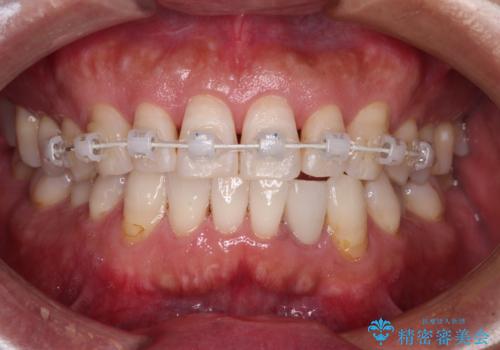

内側にある歯が干渉する 上顎前歯の部分矯正

- 矯正装置

- 審美装置

- 上顎の前歯が内側にあり、下顎のセラミッククラウンと干渉することが気になるとのことで来院された患者様です。

上顎前歯にワイヤー装置を装着し、セラミッククラウンとは干渉しないようにしながら歯列を整えることとしました。